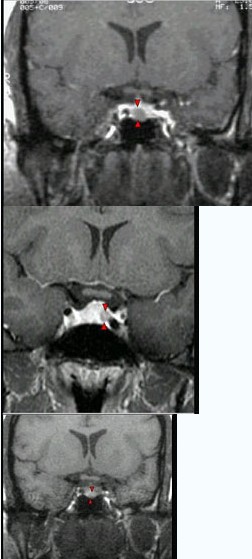

女,38岁,头痛、闭经,MRI检查如图,选择最可能的诊断()

A:垂体囊肿

B:垂体梗死

C:转移瘤

D:垂体微腺瘤

E:垂体脓肿

女性,43岁,因咳嗽、咳痰、发热1周,昏迷半天急诊入院。既往有Addison病史。查体:血压80/50mmHg,呼吸23次/分,口唇及面部皮肤可见色素沉着,左下肺可闻及少量湿啰音。抢救病人成功后应告知病人什么()。